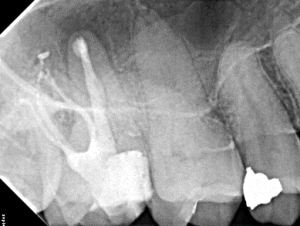

Clinical Cases